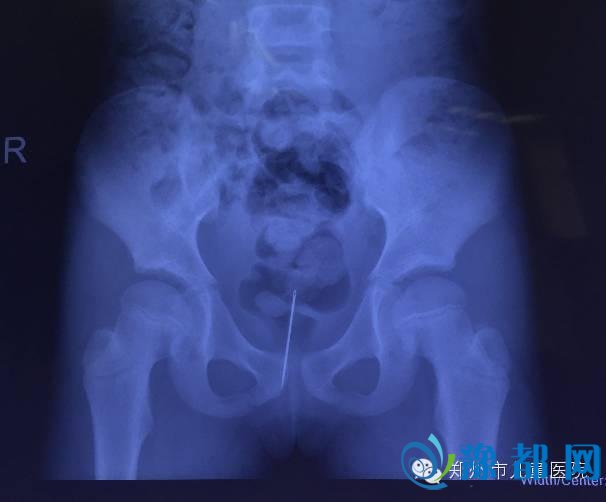

河南一名7岁女童阴道流血2年,家长带领她前往医院检查后发现,女孩阴道内竟然藏了一根缝衣针。医生称,像该例患儿阴道出现缝衣针,长期存留但无其他症状,实属罕见,家长对幼女应加强安全教育,以防类似情况发生。

2年内,家长曾带她就诊过当地多家医院,均没有查出病因。郑州市儿童医院医生对女孩进行多项检查后,在其盆腔偏下位置发现一枚家用缝衣针。

随后,女孩体内缝衣针被顺利取出。困扰她2年的阴道出血问题得到解决。但缝衣针是如何进入女孩体内的,现在无从知晓。

据郑州市儿童医院内分泌遗传代谢科卫海燕主任介绍,青春前期女孩阴道出血并非罕见,常见原因为性早熟或异物引起。儿童医院近5年接诊单纯阴道出血40余例,病因有阴道异物(棉球、布条、纸屑)、阴道肿瘤、卵巢囊肿等,像该例患儿阴道出现缝针,长期存留但无其他症状,实属罕见。